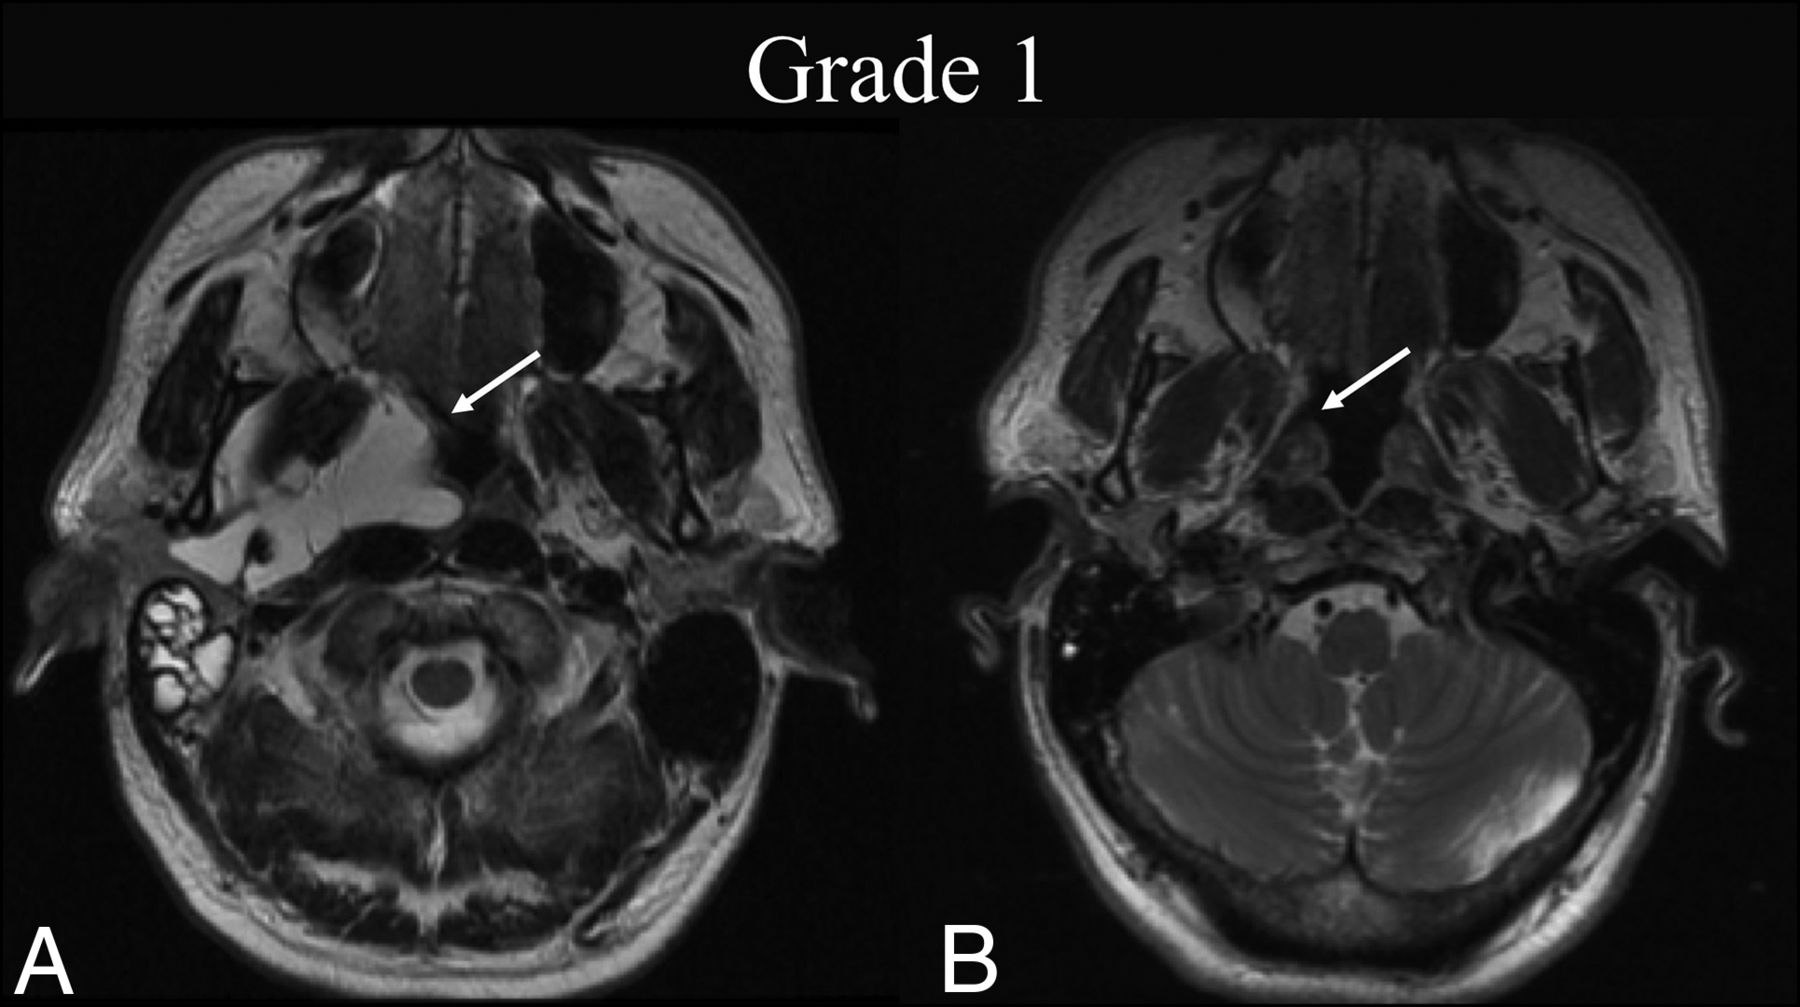

BDL grade 1 response. A 50-year-old man with dysphagia was found to have a de Serres stage II macrocystic LM of the head. A, Preprocedural T2-weighted axial MR imaging at the level of the hard palate shows a lesion primarily centered within the right parapharyngeal space (white arrow). B, Four months later, following 1 sclerotherapy treatment, T2-weighted axial MR imaging at the same level shows BDL grade 1 complete regression of the lesion on cross-sectional imaging (white arrow).